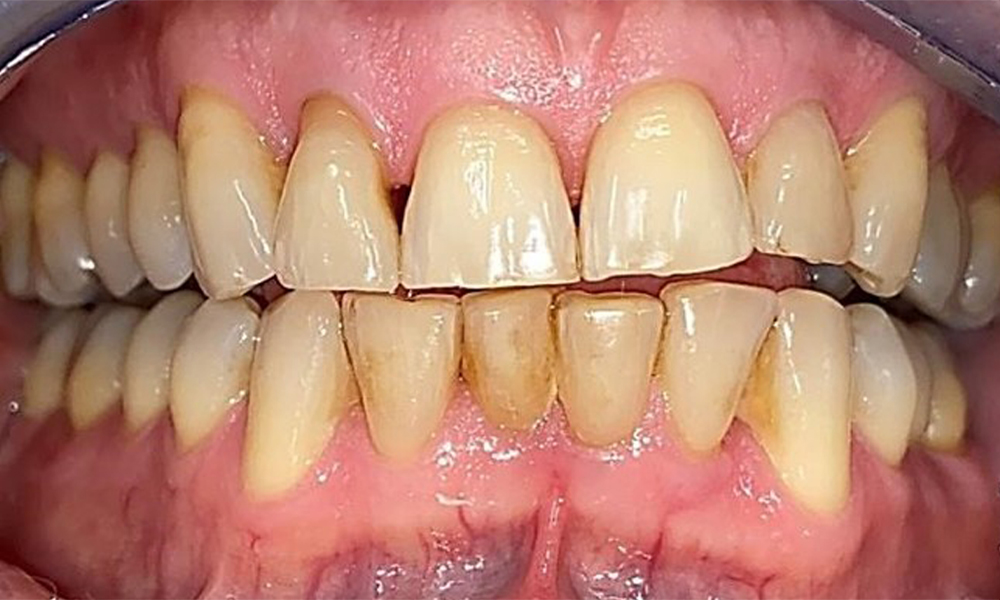

Frontal view with loss of the interdental papillae between 12 and 11.

Fig. 2 Frontal view with loss of the interdental papillae between 12 and 11. © Dr R. Krapf

The patient has a full dentition with 28 teeth, which includes amalgam and composite fillings in the molar and premolar regions. There is a visible clinical marginal gap present on tooth 14. Tooth 27 has an adequate gold inlay. There are also generalized attritions and abrasions. (Fig. 2, Fig. 3, Fig. 4, Fig. 5, Fig. 6)

The patient has stage II, grade B periodontitis (5). At 1 to 3 mm, the clinical probing depths were within the physiological range. Localized probing depths of 5 mm were observed on the mesiopalatal aspects on both 17 and 27. There are generalized recessions of 1–3 mm with partial loss of the interdental papillae (Fig. 2, Fig. 3, Fig. 4)